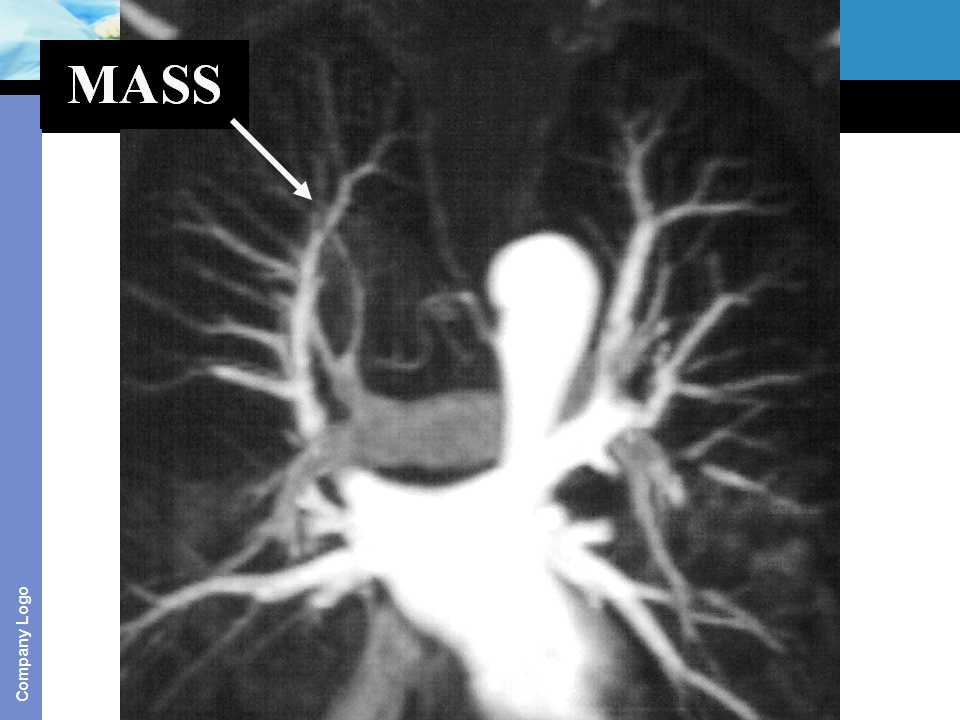

肺癌影像诊断